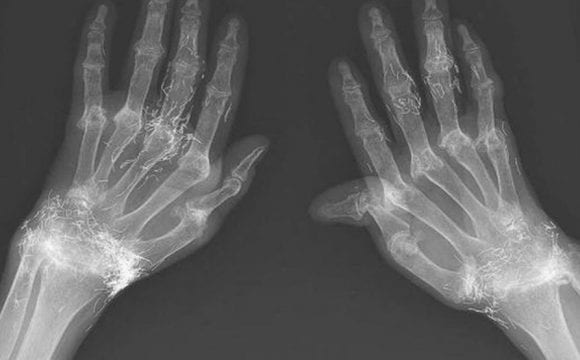

Forte dolore alle mani: dalla lastra spunta fuori l’assurdo, residui di… Chicche di Velvet Forte dolore alle mani: dalla lastra spunta fuori l’assurdo, residui di… Redazione 18 Maggio 2020 Questa donna avverte un forte dolore alle mani, ma quando si reca in ospedale scopre qualcosa di...Read More